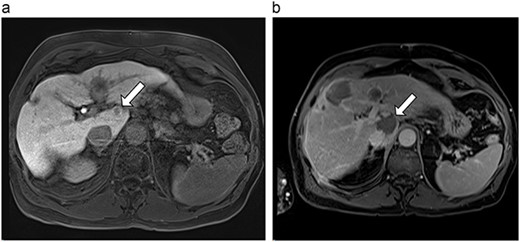

(a) Pre-ablation MRI demonstrating 14 mm lesion in caudate lobe of liver. (b) Post-ablation MRI (23 days postoperatively) demonstrating 23.8 mm complete ablation of caudate lesion.

| 4 (6a,b) | 51, M | Colon adenocarcinoma | 6 cycles FOLFOX | 4 | Laparoscopic microwave ablation | 14 | 23.8 | 9.8 | 13 | Yes |